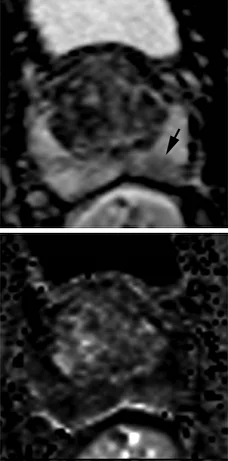

Peripheral Zone (PZ)

Очаг гипоинтенсивен на ADC, изо- или гиперинтенсивен на DWI. Либо сильно гипоинтенсивен на ADC, либо сильно гиперинтенсивен на DWI, но не одновременно и там и там.

Очаг выраженного ограничения диффузии (гипо- на ADC, гипер- на DWI), менее 1.5 см

То же что и PIRADS 4, только размером более 1.5см